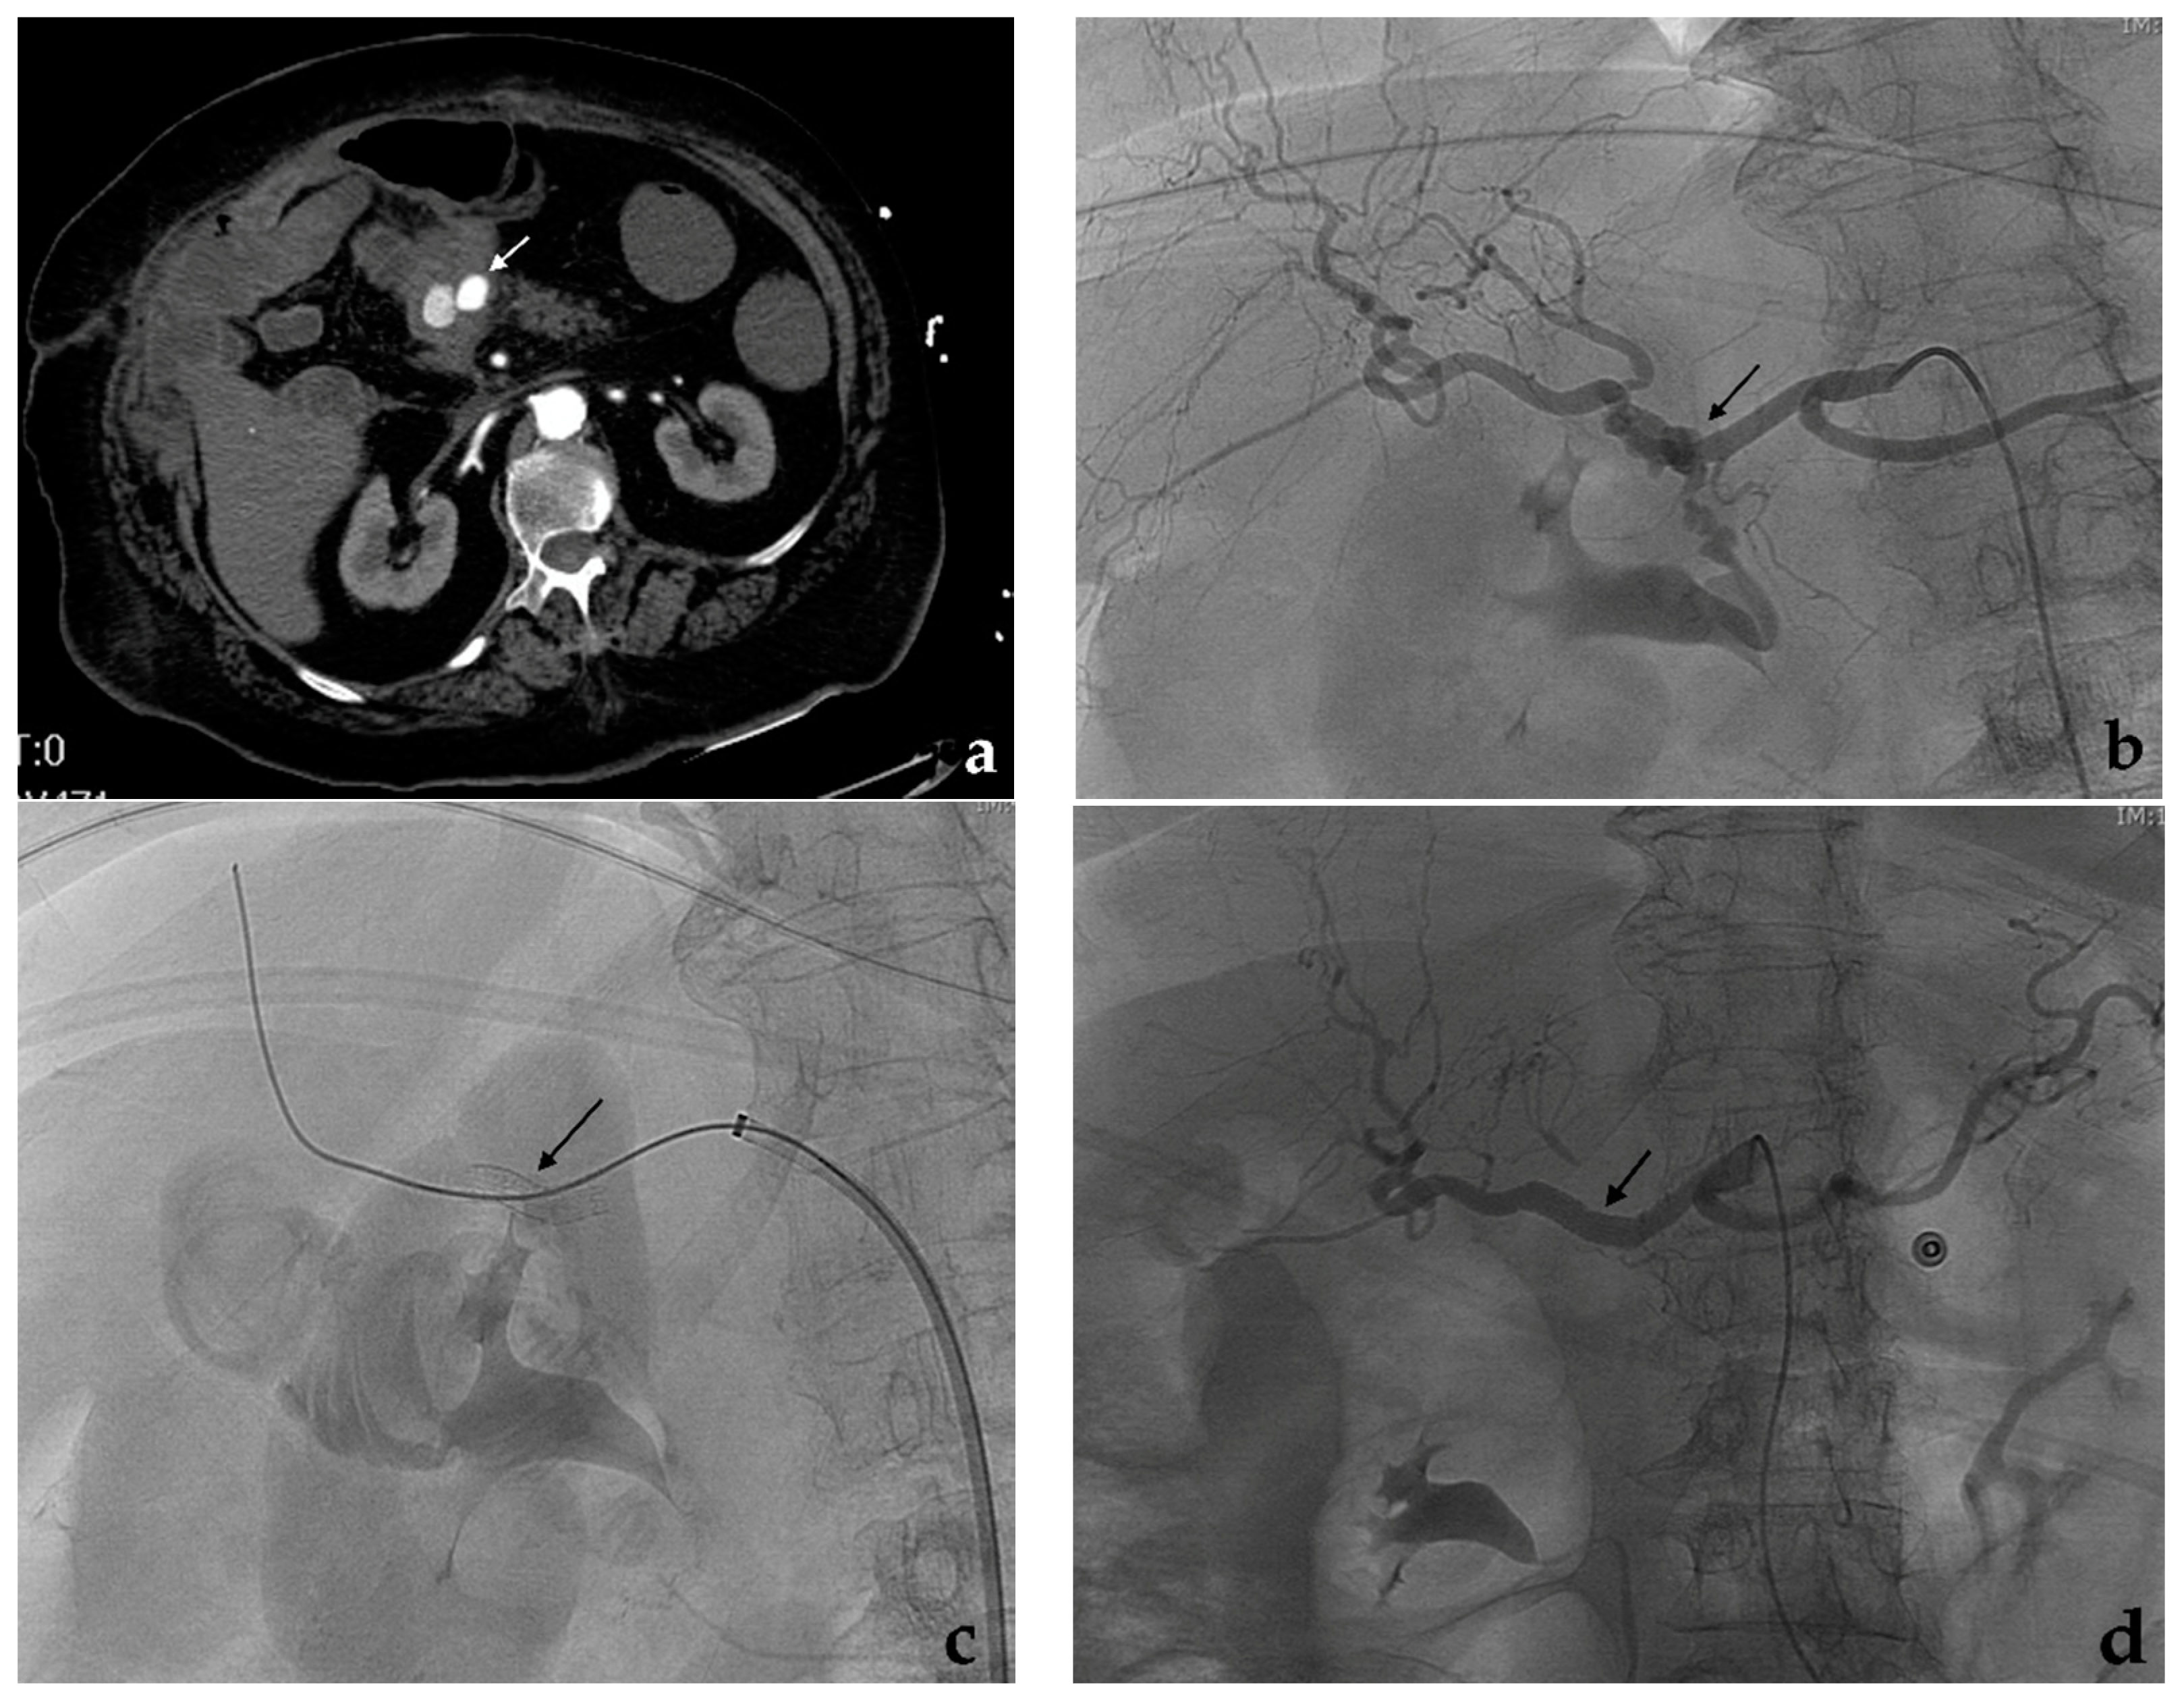

7.8. Renal Artery

- Gorsi, U.; Agarwal, V.; Nair, V.; Kang, M.; Kalra, N.; Sreedhara, B.C.; Gupta, R.; Rana, S.S.; Dutta, U.; Sandhu, M.S. Endovascular and percutaneous transabdominal embolisation of pseudoaneurysms in pancreatitis: An experience from a tertiary-care referral centre. Clin. Radiol. 2021, 76, 314.e17–314.e23. [Google Scholar] [CrossRef]